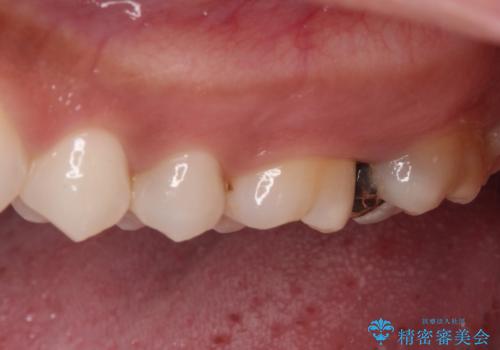

- 奥歯にフロスが引っかかるようになり、虫歯ではないかとのことで来院された患者様です。

レントゲン写真より、左右奥歯にむし歯があることが分かりました。

奥で目立たないことから、虫歯の再発リスクが最も低く、咬合力による歯への負担も少ないゴールドインレー(PGAインレー、白金加金インレー)にて修復治療をすることとしました。